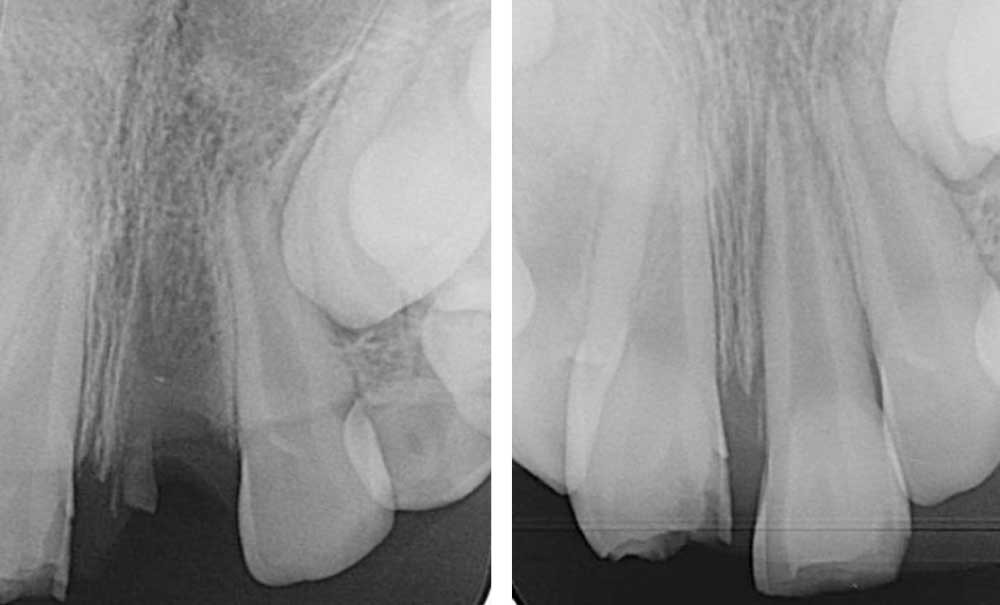

Les résorptions radiculaires inflammatoires externes surviennent après un traumatisme sévère comme une avulsion (fig. 1) ou une luxation [3], où la couche protectrice de précément et le parodonte sont altérés. Ces traumatismes peuvent provoquer une compression tissulaire au niveau du ligament parodontal, induisant des lésions vasculaires, une hypoxie et une perte d’intégrité du cément. Si la dent est restée vivante alors, un processus de réparation se met en place avec l’apposition d’un nouveau cément et d’une nouvelle attache. En revanche, si la dent venait à se nécroser, alors les stimuli pro inflammatoires résultant de l’activité des bactéries au sein du canal vont diffuser à travers les tubuli dentinaires et rejoindre les zones de résorption externe, et ainsi vont aggraver le processus résorptif qui est déjà actif [4].

Les RREI se manifestent par des signes de parodontite apicale : douleur, gonflement, sensibilité à la percussion ou à la palpation, fistule ou dyschromie de la couronne. En général, la dent affectée présente une réponse négative aux tests de sensibilité pulpaire [5]. L’examen radiographique montre des zones radioclaires irrégulières (aspect déchiqueté) autour de la racine lorsque la résorption est active. Le canal radiculaire reste visible et bien identifiable. Dans les cas avancés de résorption, la racine peut être complètement résorbée. Un examen 3D (CBCT : Cone Beam Computed Tomography) est recommandé pour aider au diagnostic et à la prise en charge de la RREI qui, cliniquement, semble traitable [6].